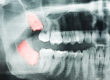

Although this is a routine procedure, wisdom teeth extraction is a serious proposition for patients. While the recovery period is relatively short, patients still need to be prepared for some downtime, and they need to know what steps to take to ensure an uneventful recovery.

The timing of the surgery may also influence your recovery. If you have your wisdom teeth removed before age 25, as is recommended by dentists, you will heal more quickly and you’ll have a lower risk.